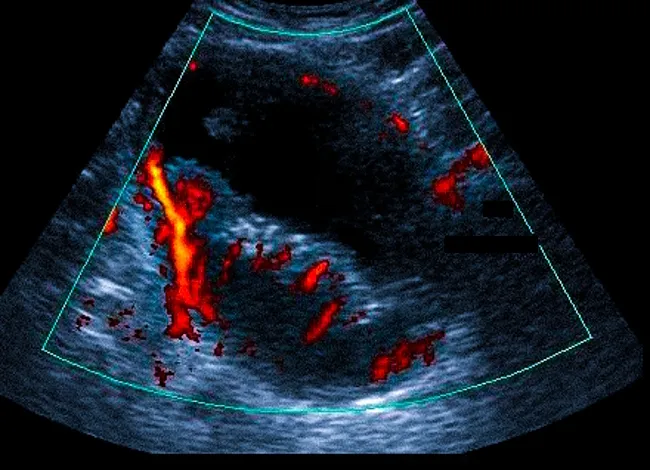

Злокачественное образование, напоминающее цветную капусту в мочевом пузыре с развитой сосудистой сетью, что может быть выявлено при допплерографии.